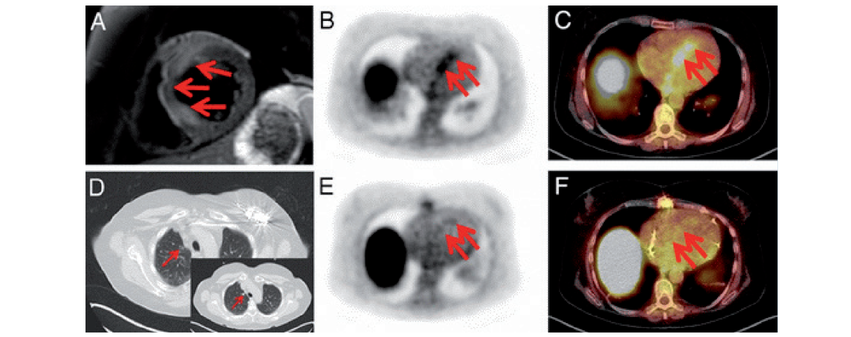

A) MRT-Aufnahme der kurzen Herzachse (wassergewichtet). Die roten Pfeile verweisen auf Wassereinlagerungen (Ödeme) aufgrund einer Entzündung. B) PET-Aufnahme mit vermehrter 68Ga-DOTA-TOC-Marker-Aktivität (rote Pfeile), die auf Entzündungen hinweisen. C) Überlagerungsbild D) Rückgang der Entzündung in einer Lunge nach Cortison-Therapie (rote Pfeile; Insert: ursprünglicher Lungenbefall) E) und F) Die Entzündung im Herz ist ebenso zurückgegangen.

So bindet das radioaktive Molekül 68GaDOTA-TOC beispielsweise an Oberflächenmoleküle (Somatostatin Rezeptor 2), die auf Entzündungszellen, nicht aber auf Muskelzellen vorkommen. Mittels Positronenemissionstomographen (PET) lassen sich dadurch Entzündungen und deren Verlauf im Herzen nachweisen (Abb. 1).